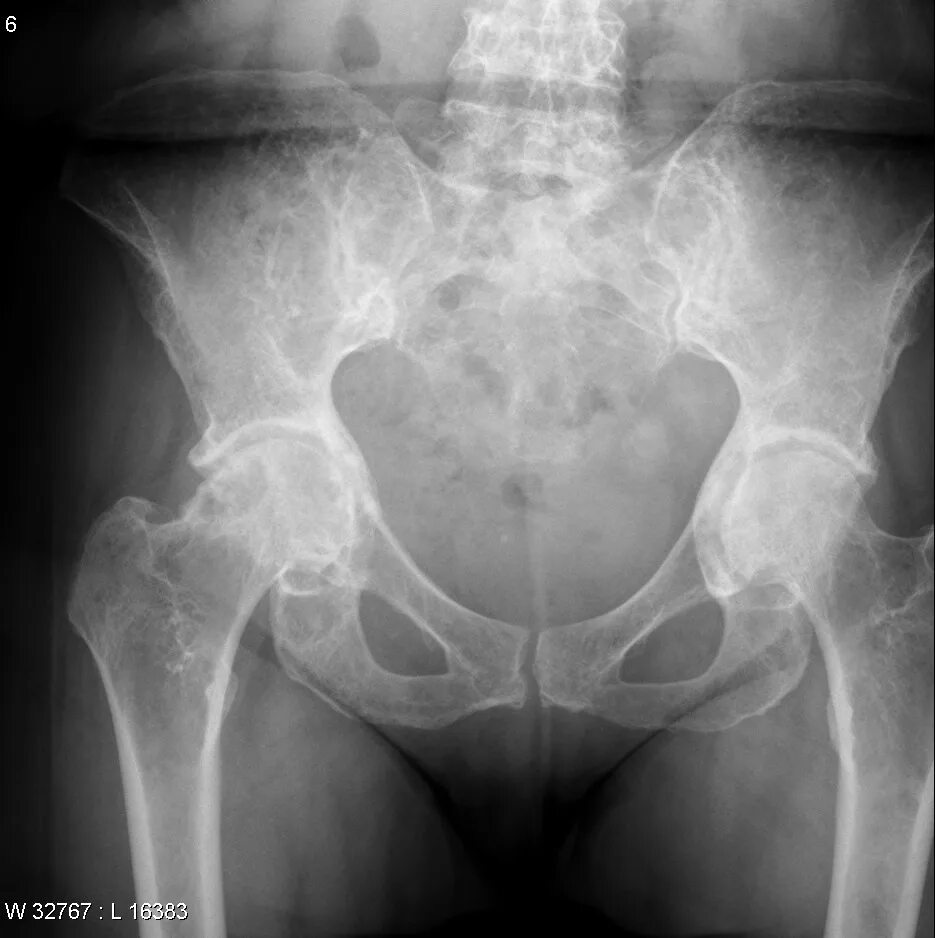

Метастазы скелета